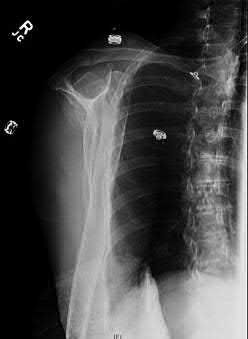

A 68-year-old osteoporotic female sustains a proximal humerus fracture. The AP radiograph is shown. According to the Hertel criteria, which of the following radiographic features is the most reliable predictor of humeral head ischemia?

Options:

- Anatomical neck fracture pattern

- Greater tuberosity displacement > 1 cm

- Metaphyseal head extension (calcar segment) less than 8 mm

- Varus angulation greater than 20 degrees

- Disruption of the medial periosteal hinge > 2 mm

Correct Answer: Metaphyseal head extension (calcar segment) less than 8 mm

Explanation:

Hertel et al. described radiographic criteria predictive of humeral head ischemia. The most reliable predictors include a metaphyseal head extension (calcar segment) of less than 8 mm, disruption of the medial hinge (>2 mm), and an anatomic neck fracture. Among the choices, the calcar segment length < 8 mm represents a highly predictive sign that the primary blood supply (the ascending branch of the anterior humeral circumflex artery and intraosseous vessels) has been severely compromised.